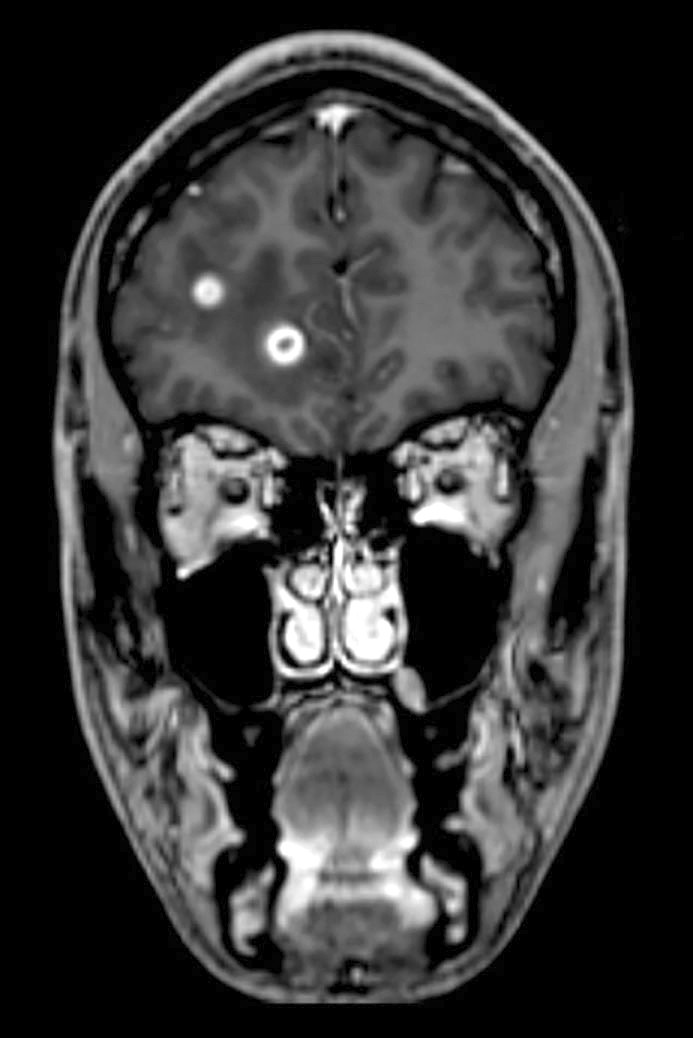

A CT scan of the head without contrast was taken immediately after admission and showed low-attenuation changes in frontal white matter in the right cerebral hemisphere (Fig. 1) and in the right cerebellar hemisphere. Supplementary magnetic resonance tomography of the brain and medulla the following day revealed multiple lesions in the brain stem, cerebellum and both cerebral hemispheres (Fig. 2). The neuroradiologist regarded the findings as consistent with multiple metastases, cerebral tuberculosis, a parasitic disease or septic emboli with secondary abscess formation. Cerebrospinal fluid analysis revealed a leukocyte level of 9 · 109/l, but otherwise normal values for erythrocytes, glucose and protein. The same evening, CT scans of the thorax, abdomen and pelvis were carried out to look for signs of extracerebral disease, including cancer, bacterial infection focus, tuberculosis in or outside the lungs, or signs of a parasitic disease. They revealed multiple micronodules in the lungs, most in the apical parts of both upper lobes, one slightly larger nodule in the apical lateral segment of in the left upper lobe and a small high-attenuation lesion to the right of the entry of the right main bronchus, consistent with a calcified lymph node (Fig. 3). There were multiple low-attenuation lesions in the abdomen and pelvis, most of them in the upper part of the liver, and in addition lesions in the kidneys and prostate. The radiologist described the findings as most consistent with miliary tuberculosis.

Figure 2 T1-weighted volumetric magnetic resonance tomography of brain and medulla, taken with contrast medium. The image…

Figure 2 T1-weighted volumetric magnetic resonance tomography of brain and medulla, taken with contrast medium. The image shows multiple lesions in the cerebral hemisphere.